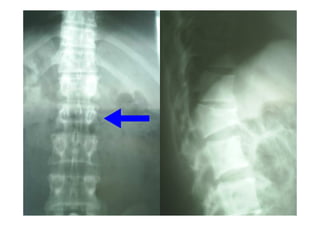

TÓRACO-LOMBAR

TIPOS DE FRATURAS

FRATURAS